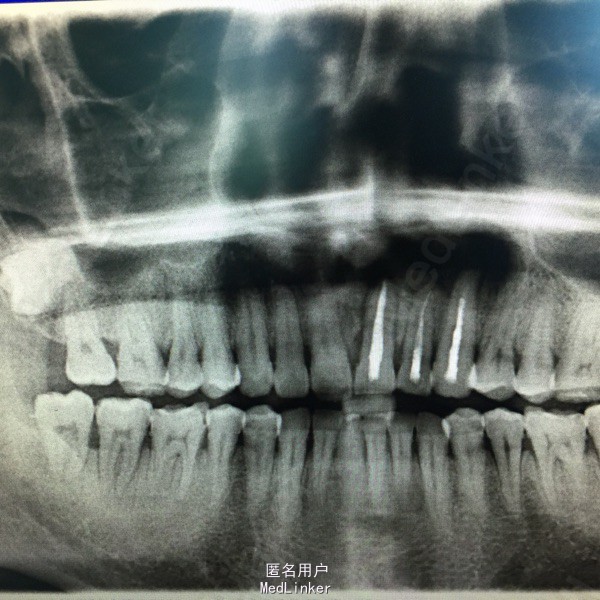

诊断:21、22、23根尖囊肿。 处理:患牙行根管治疗。 完善术前准备,口服抗生素1天,择期行根尖囊肿开窗减压术。